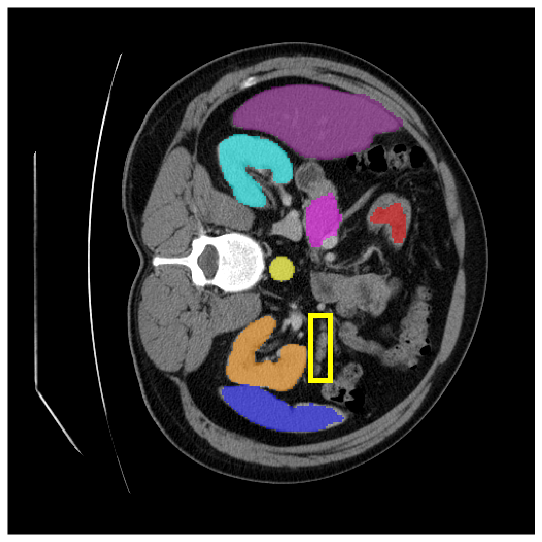

4.3.2 Visual Comparisons

Visualization of our method on the Synapse and ACDC datasets is shown in Fig. 3(a) and Fig. 3(b). For the Synapse dataset illustrated in Fig. 3(a), FCT failed to accurately segment SM and GB, while MERIT achieved precise segmentation of SM but struggled with GB. In contrast, our method achieved accurate segmentation of both SM and GB. Regarding the ACDC dataset shown in Fig. 3(b), while previous methods achieve comparable segmentation of the Myo and LV to the GT, they exhibit noticeable errors on the RV, including invasion into adjacent organs and misrecognition. On the other hand, our method accurately segments across all three structures Myo, LV, and RV, performing as precisely as the GT. We demonstrate the superiority of our method quantitatively and qualitatively.